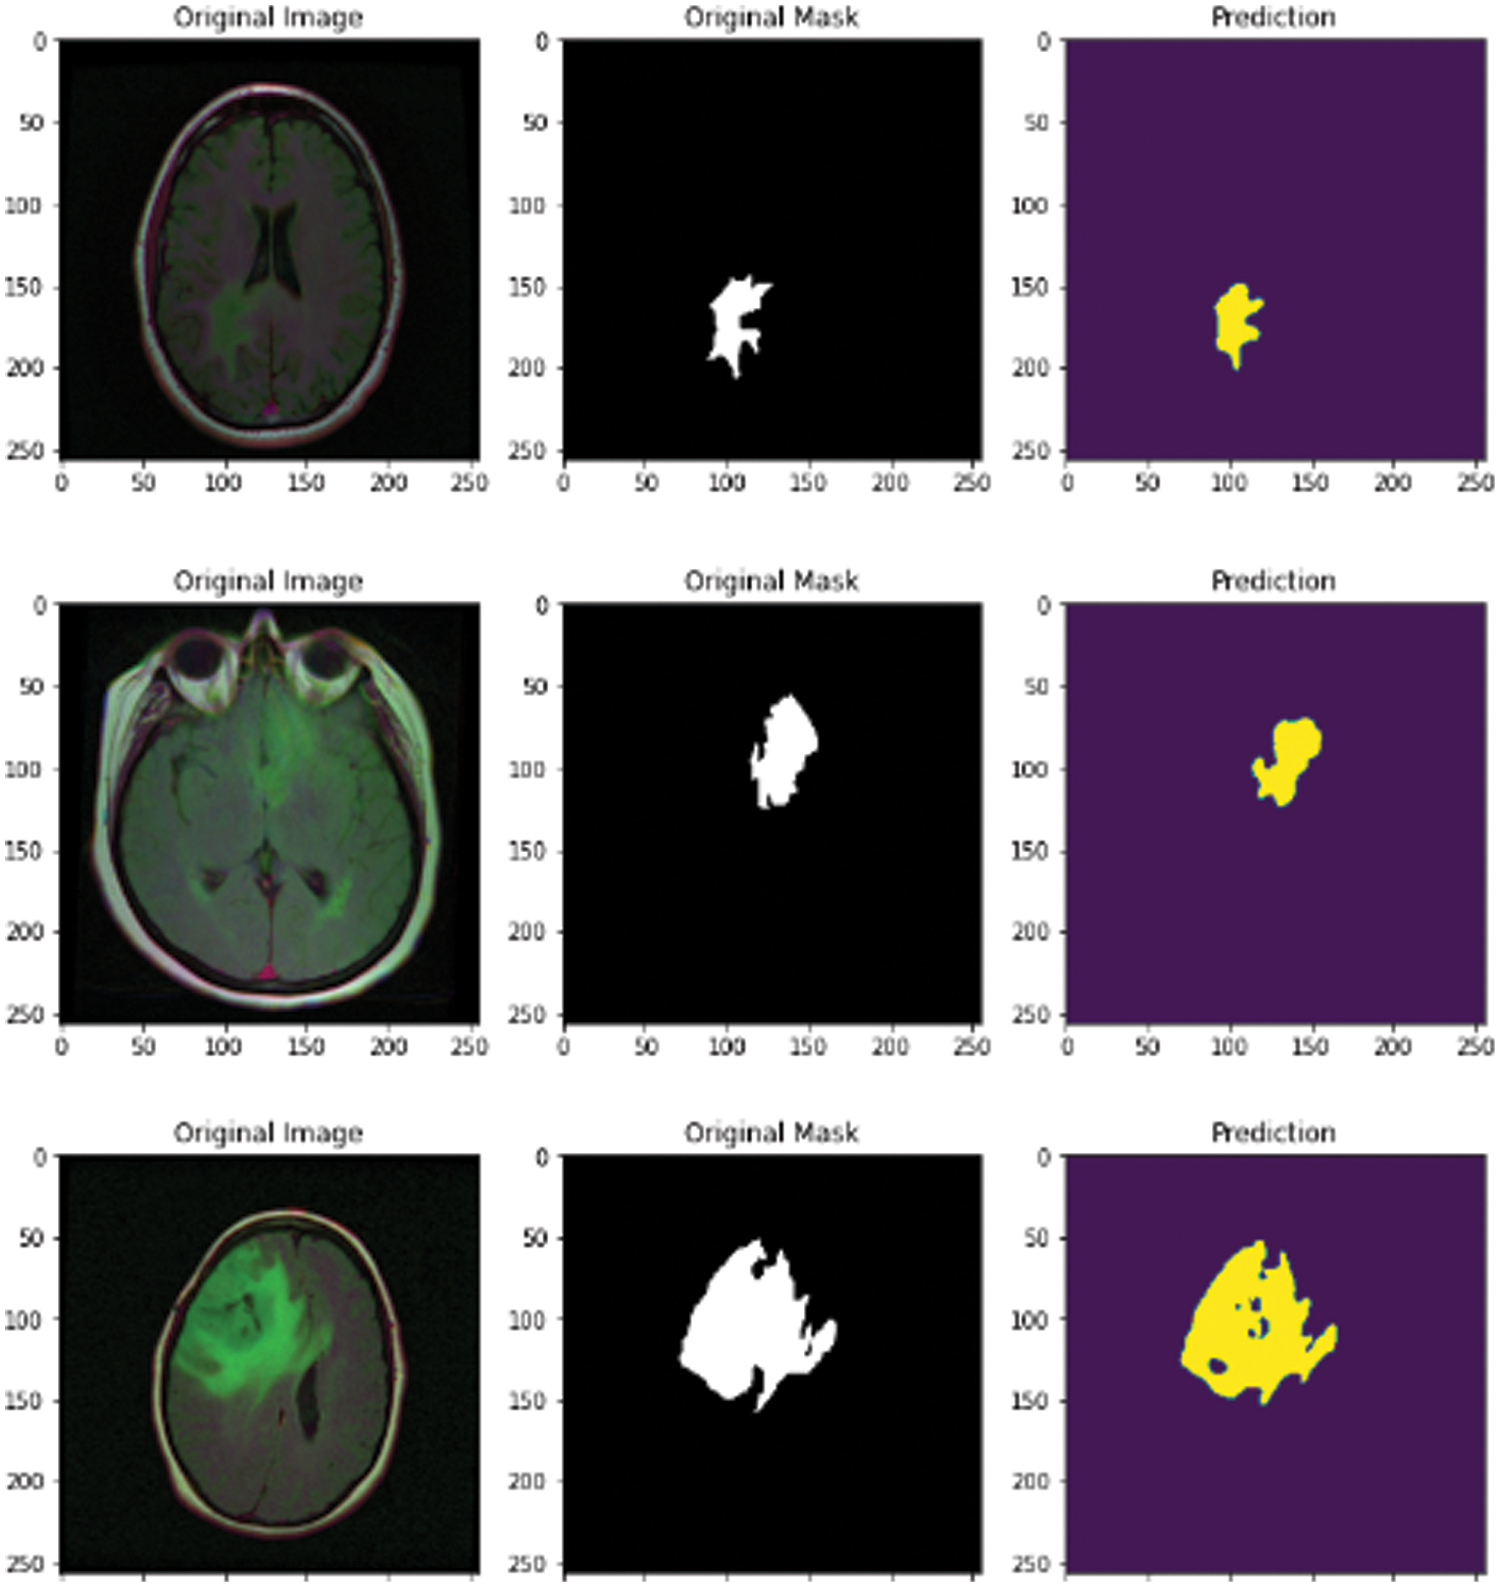

3.2 Results of the Segmentation Step

In this subsection, the novel framework shows the final results after using the attention-U-Net deep learning model for segmentation of the MRI images after reducing the speckle and Rician noise in the previous stages. The attention U-Net with the previous method of reducing the noise has achieved an accuracy of nearly 94.66, which is better than the accuracy of U-Net and the accuracy without the previous model for removing the noise. Fig. 12 shows the predicted mast, mask, and the original image. The novel framework has achieved results in dice scores better than the previous versions of U-Net. The attention U-Net has achieved accuracy better than U-Net and residual U-Net. A U-Net and residual U-Net have been achieved 93.23 and 93.45 in accuracy, respectively.

Figure 12: MRI original image, mask, and predicted mask